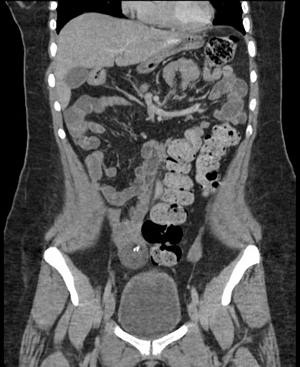

The protocol is complemented with an extension study using an abdominal-pelvic CT scan, documenting a heterogeneous tumor dependent on the right annex with multiple calcifications inside, suggestive of teratoma (Figures 3 and 4).

Figure 3 Abdominal and pelvic CT in axial section showing a heterogeneous tumor dependent on the right ovary, round with defined edges with calcium density (393 HU) inside.

Figure 4 Abdominal and pelvic CT in coronal section showing a heterogeneous tumor dependent on the right ovary with a hyperdense calcium image (393 HU) inside, with peripheral enhancement to the contrast and with dimensions of 3.9 x 3.6 x 4.3 cm and a volume of 30cc.